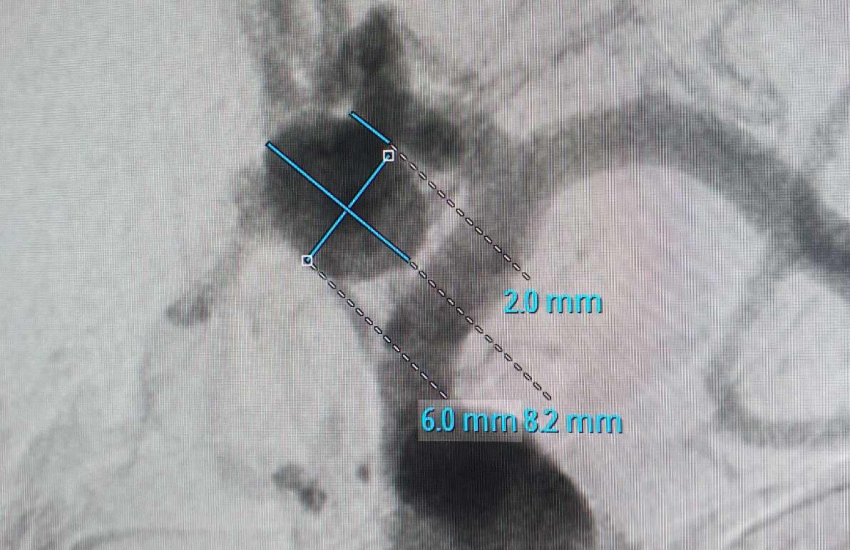

Пацієнт розповів, що його довгий час турбували сильні головні болі та з огляду на повторні інсульти у його близької родички, він вирішив не зволікати, звернувся на консультацію до нейрохірурга і пройшов комп’ютерну томографію головного мозку. За результатами обстеження і була виявлена аневризма артерії головного мозку.

За словами завідувача відділення інтервенційної радіології Черкаської обласної лікарні Паляничка Дмитра Андрійовича, операцію було виконано найбезпечнішим і сучасним способом, зробивши прокол артерії кисті пацієнта, через який хірурги потрапили до цільової судини в головному мозку та імплантували мікроспіралі, вилучивши аневризму з кровообігу та попередивши її розрив та інсульт. Хірург зауважив, що такі операції, на відміну від відкритих, з трепанацією черепу, в рази знижують ризик як самої операції, так і післяопераційних ускладнень. Вже через пару годин після операції пацієнт повернувся до звичайного життя та був виписаний на другу добу додому.